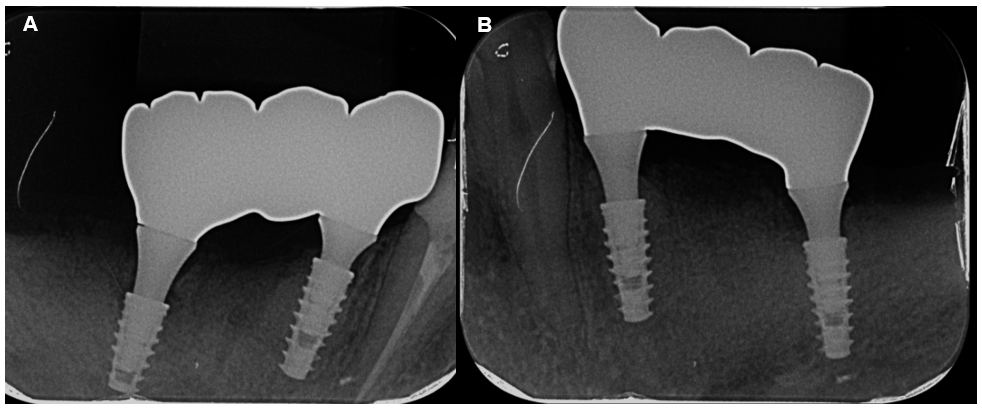

Conforme o plano de tratamento, os implantes estariam localizados nas regiões correspondentes aos dentes 11, 14, 21 e 24, utilizando a técnica All-on-4. Os implantes utilizados foram da Implacil De Bortoli: Due Cone – Maestro CM Base T 4.5 Ø 3,5x11mm para os incisivos centrais e Ø 3,5x13mm para os pré-molares.

A cirurgia foi realizada por meio da técnica flapless, cirurgia de campo fechado, e foi feita a instalação do implante, iniciando com a fresa lança helicoidal de 2mm associado ao guide referente. Foi realizado a conferência da perfuração e, por fim, a fresagem com a fresa cônica de 3,5mm, conforme o tamanho pré-determinado dos implantes, respeitando a distância da margem gengival em relação ao implante e o seu posicionamento.

Após três meses, período adequado da osseointegração e a verificação radiográfica, foram realizadas todas as etapas referentes a prótese, dentre elas: reabertura, escaneamento, moldagem, registro de mordida, prova dos dentes e instalação do protocolo.